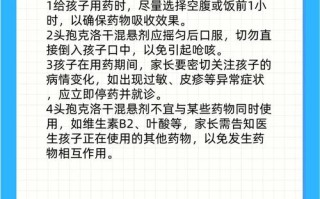

设计理念

- 款式:经典简洁的包屁衣连体裤,适合0-3岁的婴幼儿。

- 季节:夏季,因此我们选择纯棉、纱布、天丝等透气亲肤的面料。

- 细节:

- 按扣门襟:从裆部延伸到胸口,方便穿脱,尤其适合小宝宝。

- 包边处理:所有缝份都用包边条或包边机包边,防止毛边,更美观舒适。

- 无袖设计:凉爽透气,适合炎热的夏天。

- 松紧裤脚:可以调节松紧,适应宝宝不同阶段的成长,且舒适不勒腿。

(图片来源网络,侵删)